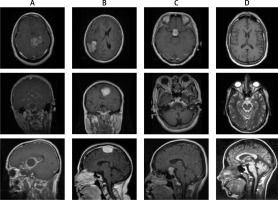

A brain tumour is a mass of abnormally growing cells in the brain or skull. Some brain tumours are harmless, while others are dangerous. Tumours can start in the brain itself (primary) or the cancer can spread from another part of the body to the brain (metastasis). Treatment options depend on the type of tumour, its size, and its location. The World Health Organization made a classification and grading system to make it easier to converse about brain tumours, plan treatments, and predict how they will turn out. Figure 1 shows how tumours are categorised by the type of cells they are made of or where they started.

The brain dataset investigated in this study is collected from the Figshare repository [3]. The dataset comprises TI-weighted MRI of no tumour and 3 different types of tumours: meningioma, glioma, and pituitary. Image resolution of 512 × 512 with different views such as axial (transverse plane), coronal (frontal plane), or sagittal (lateral plane) planes was used in this dataset. The sample distribution based on the number of classes consisted of 826, 822, 827, and 395 sample instances of glioma, meningioma, pituitary, and no tumours, respectively. The sample of 3 types of brain tumour is shown in Figure 2.